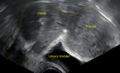

A very large (9 cm) fibroid of the uterus which is causing pelvic congestion syndrome as seen on ultrasound